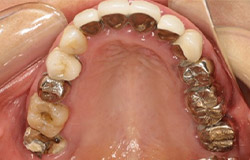

インプラントで噛み合わせの再構成を伴った症例。

治療後のメンテナンスを行わないと

周囲炎になるリスクあり。